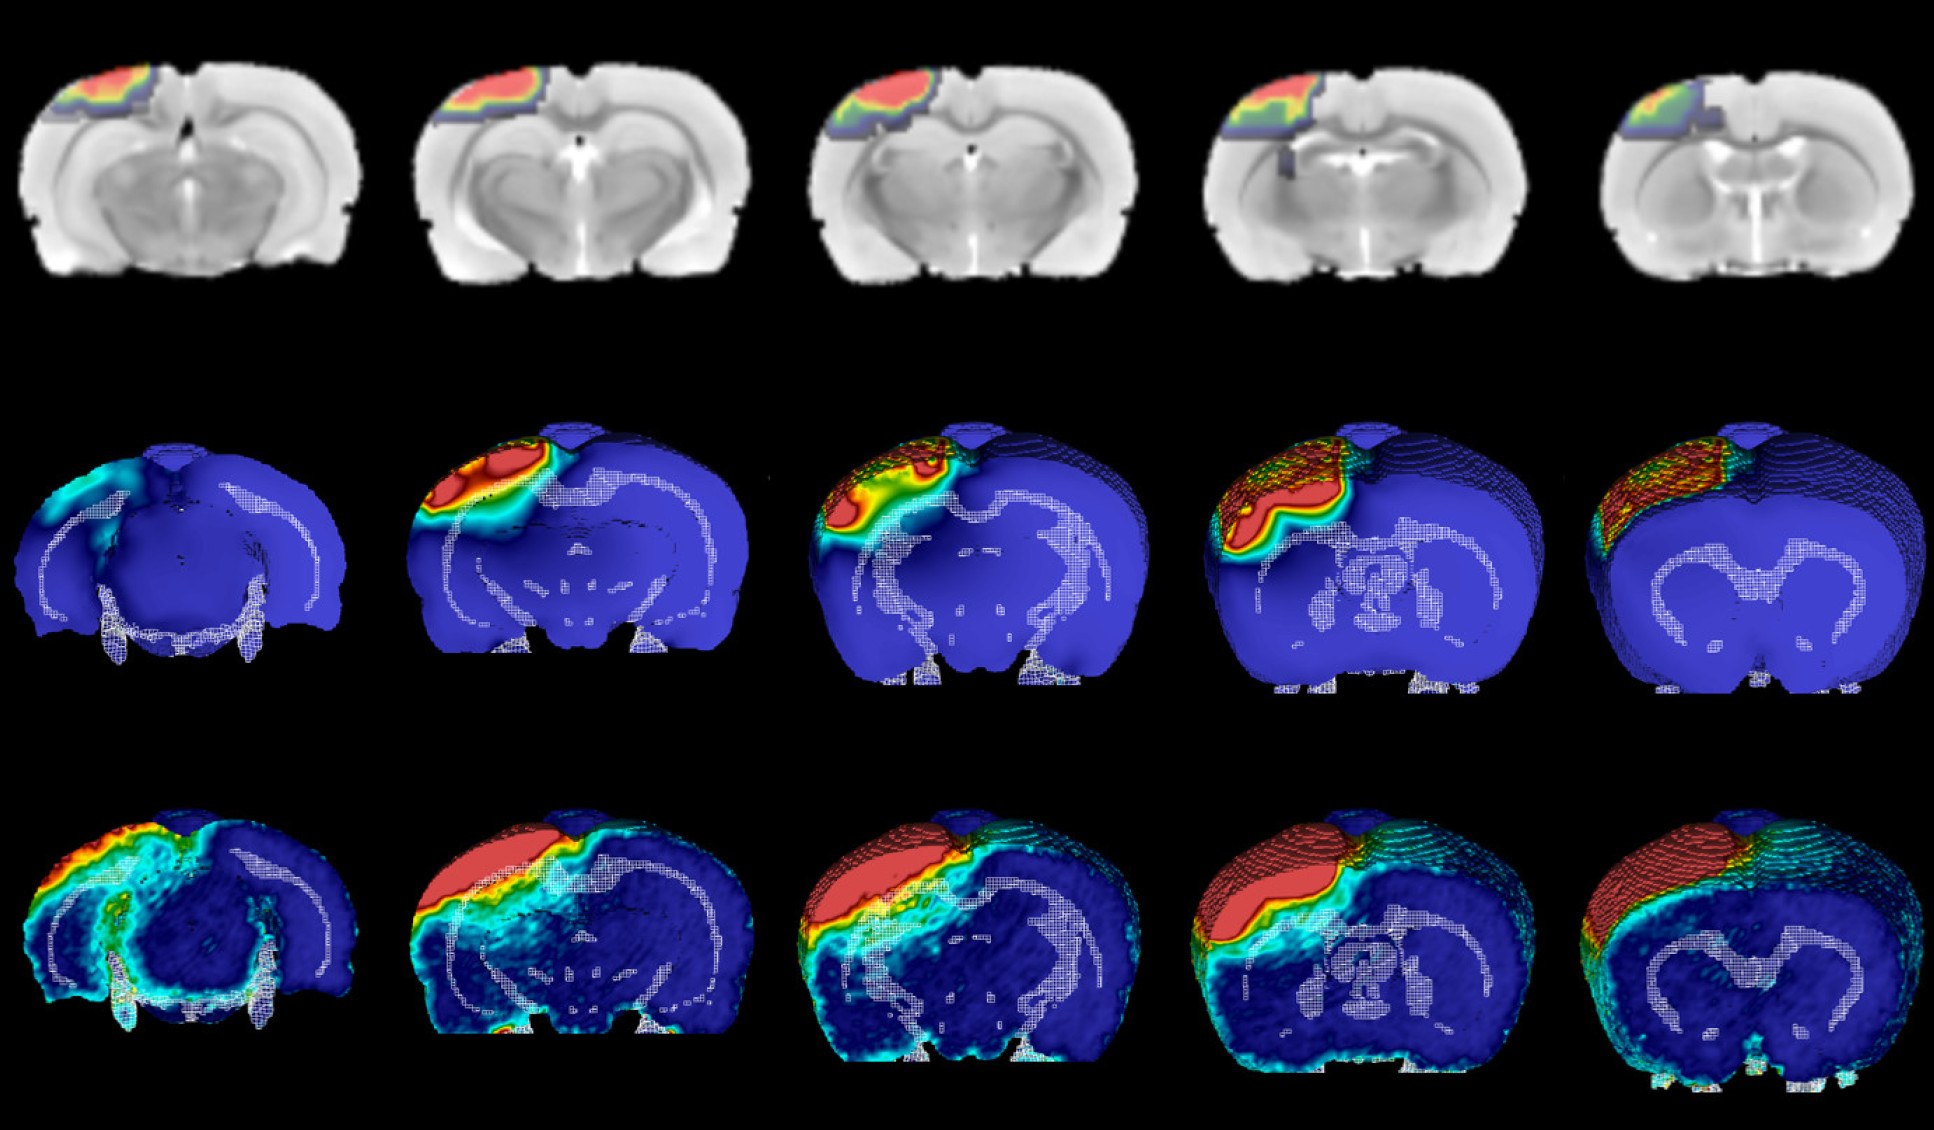

Imaging and computational models depicting the development of brain injury after a moderate impact on rat brains.

Imaging and computational models depicting the development of brain injury after a mild impact on rat brains.

Development of injury after mild impact

Now, they have tested this modelling approach to see if it can accurately predict the pattern of white matter damage in rats given mild or moderate TBI. They simulated the rats’ brains during injury, revealing the location and duration of mechanical forces linked to damage. Using a precise experimental model, this damage was induced in the rat brain and followed up after several weeks, which correlates to years of changes in a human brain.

They found that the effect of shear stresses on the white matter helped to predict the location of long-term damage. Shear stresses push two parts of the same object, in this case the brain, in different directions.